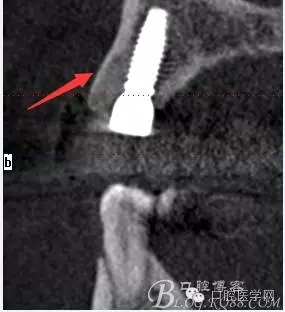

術后片顯示方向非??梢?/p>

頰顎向的方向也很理想 箭頭所示 空間填滿了自體骨